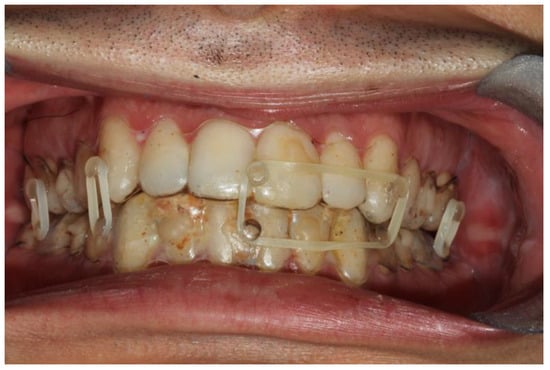

Figure 2. Intraoral view of patient 1; the fitting of the splints is adequate and so is the fixation.

The first patient was a woman with a right sub-condylar non-displaced fracture, with sound permanent dentition, and without comorbidities (Figure 3). She had already received orthodontic treatment for agenesis of the upper lateral incisors, with space closure by means of mesialization of the upper teeth. She had a molar class II, the upper canines in the place of lateral incisors, and a deep bite. In this case, the application of a fixed orthodontic appliance would have implied the need to be absolutely passive in order not to compromise the result of the orthodontic therapy. Furthermore, the anterior deep bite would have been an impediment for the correct positioning of the brackets on the lower incisors.

The fixation strength of the intermaxillary fixation was considered adequate in both cases (Figure 5 and Figure 6).

Occlusion and periodontal tissue were within normal clinical ranges after the treatment (Figure 6).